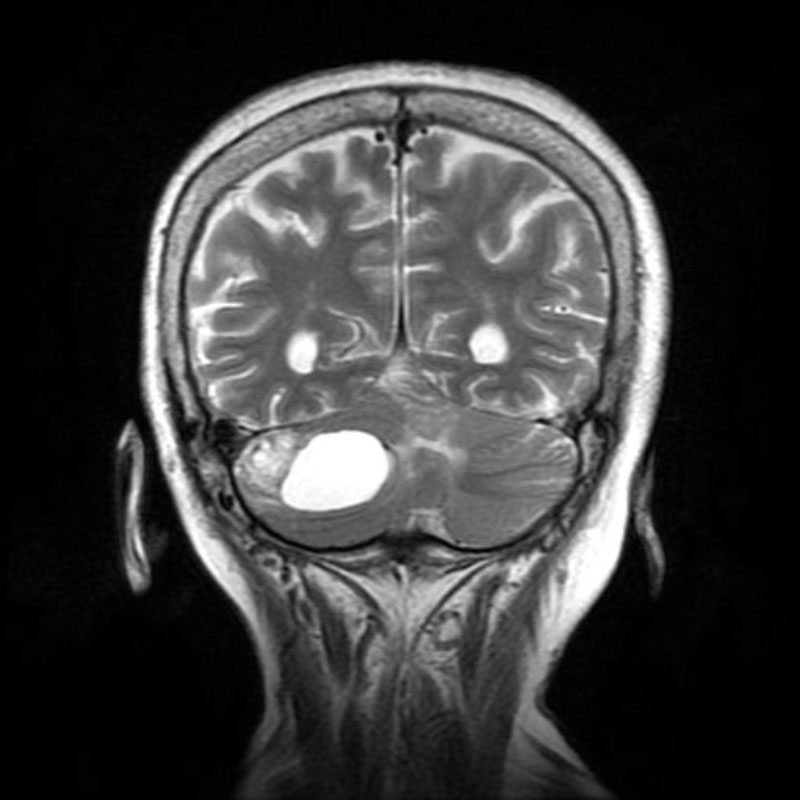

症例 '25年10月

No.

673

’25_75

'25年10月

80代

病名

術式

備考

小脳腫瘍

頭蓋内腫瘍摘出術

断層撮影

手術後